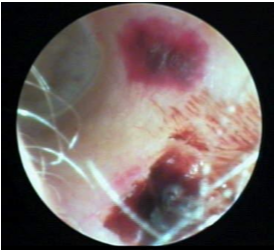

herpes Zoster Oticus

Rash or blisters on the skin of the ear canal. Ear pain, burning sensation, vertigo, tinnitus, facial weakness, ipsilateral hearing loss